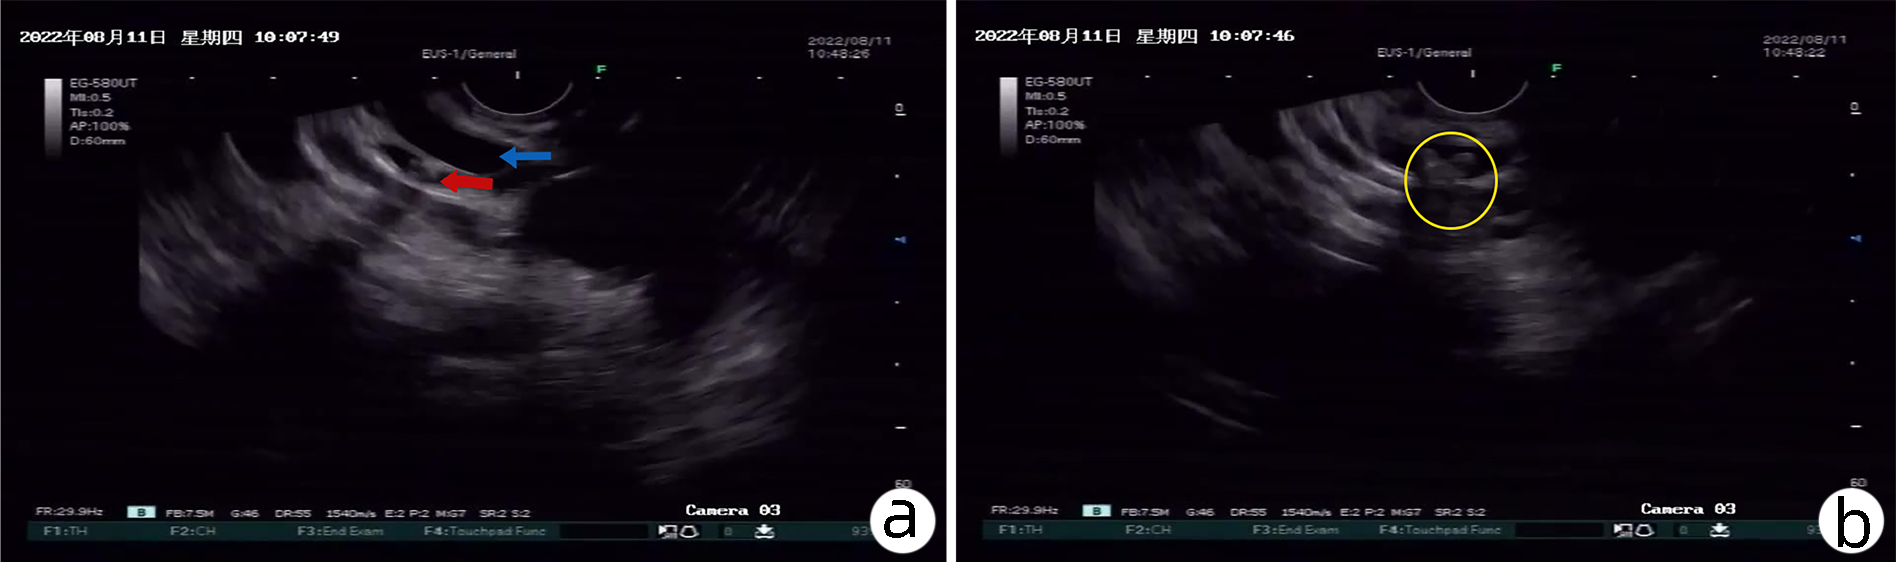

内镜逆行胰胆管造影联合SpyGlass确诊胆囊黏液腺瘤1例报告

卢心毓, 王林恒, 江贵, 云逸飞, 黄朔, 张丽杰

2023, 39(5): 1162-1165. DOI: 10.3969/j.issn.1001-5256.2023.05.025

摘要(806) HTML (370) PDF (2680KB)(63)

摘要: